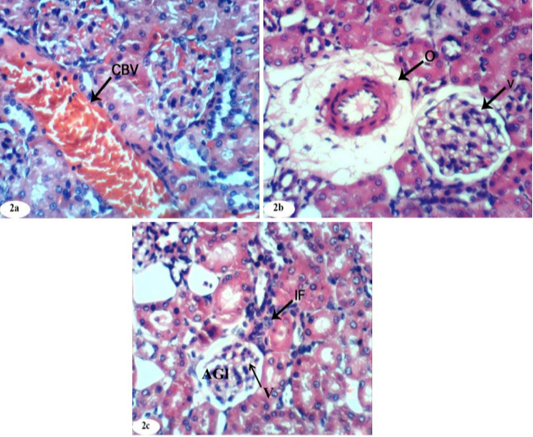

Photomicrographs of kidney sections of doxorubicin-injected group showing dilation and congestion (CBV) of renal blood vessel (Photomicrographs 2a), vacuolation (V) of endothelial lining glomerular tuft, perivascular oedema (O) (Photomicrograph 2b), peritubular mononuclear inflammatory cells infiltration (IF) and atrophied glomeruli (Photomicrograph 2c). (H and E X 400).